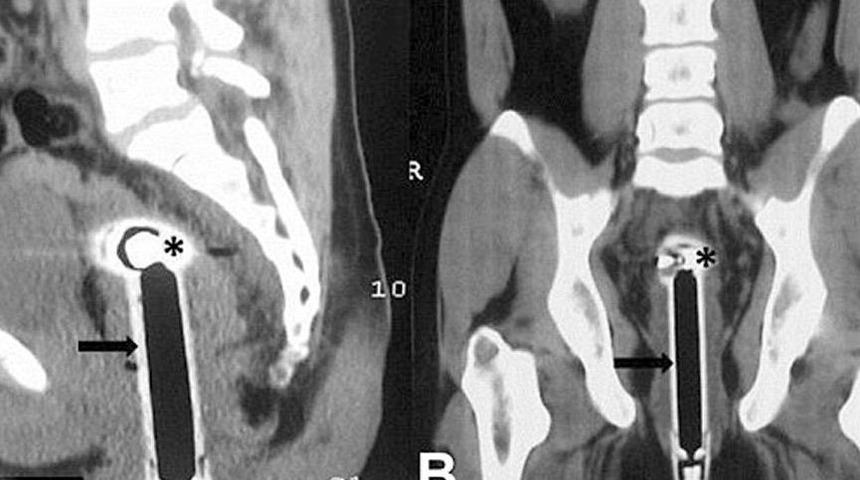

Hindistan’da 26 yaşında ismi açıklanmayan bir adam, banyoda kayarak duş başlığının üzerine düştüğünü söyleyerek hastaneye gitti.

Doktorların yaptığı incelemeler sonucunda, duş başlığının adamın rektumundan 15 santimetre kadar içeri girdiği tespit edildi.

Başarılı bir operasyon geçirdiği açıklanan adamın sağlık durumunun iyi olduğu ifade edildi.

Konuyla ilgili açıklamalarda bulunan doktorlar, adamın hikayesinin inandırıcı gelmediği ve ‘muhtemelen’ yaşanan olayın ‘kaza olmadığı’ yönünde görüş belirtti.